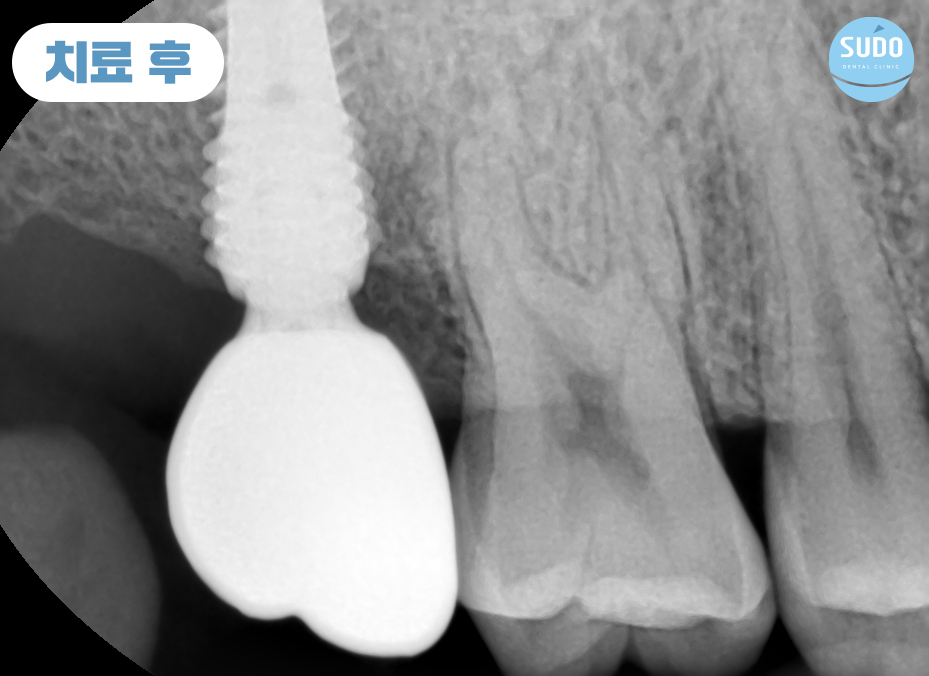

최종 보철물을 장착하고 모든 과정을 마무리한 모습입니다.

임플란트를 단단하게 오랜기간 동안 사용하기 위해서는 인공치근과 잇몸뼈와의 융합이 매우 중요합니다. 잘 융합되어 단단하게 고정되어야 문제없이 사용이 가능하기 때문에 인공치근이 안정적으로 자리 잡을 수 있도록 기다려준 뒤 보철물을 장착합니다.

환자분께서는 잇몸뼈에 단단하게 고정된 임플란트로 편안한 식사에 만족도가 매우 높으셨으며, 주변 치아와의 크기와 색깔도 자연스러움에 감사의 인사를 전해주셨습니다.